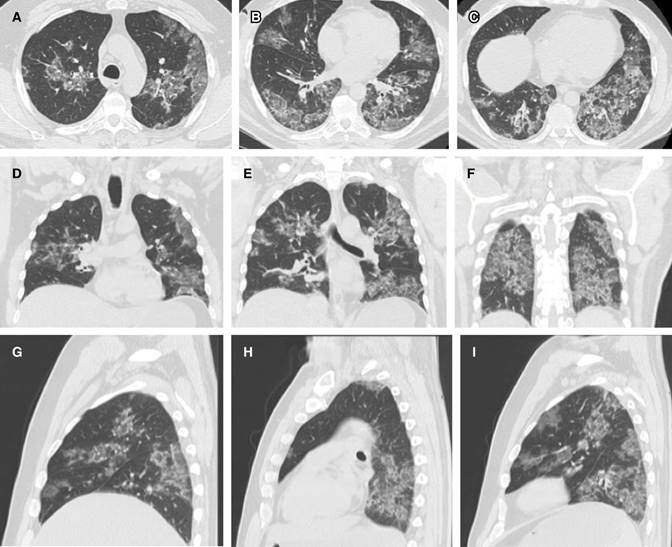

Sus imágenes radiológicas pueden observarse en la Figura 2 y consistieron igualmente de imágenes en vidrio despulido, en parches bilaterales y profusos, abarcando prácticamente todas las regiones del pulmón. Evolucionó sin taquipnea ni disnea. En la actualidad se encuentra estable, con mejoría importante de la tos y afebril, refiriendo fatiga y debilidad muscular particularmente en las extremidades inferiores. Uno de sus hijos resultó positivo 11 días después, con un cuadro muy leve y manifestaciones en piel.

Figura 2: Cortes tomográficos del caso 2 al séptimo día de evolución. El cuadro clínico del COVID-19 puede empeorar a partir de la segunda semana de evolución, en la cual habrá que estar particularmente atentos ante el inicio de disnea. Se aprecian cortes axiales ápico-caudales (A-C), coronales antero-posteriores (D-F) y sagitales derecha a izquierda (G-I); obsérvense los amplios infiltrados en vidrio deslustrado bilaterales generalizados, cuyo carácter periférico ha empezado a perderse.